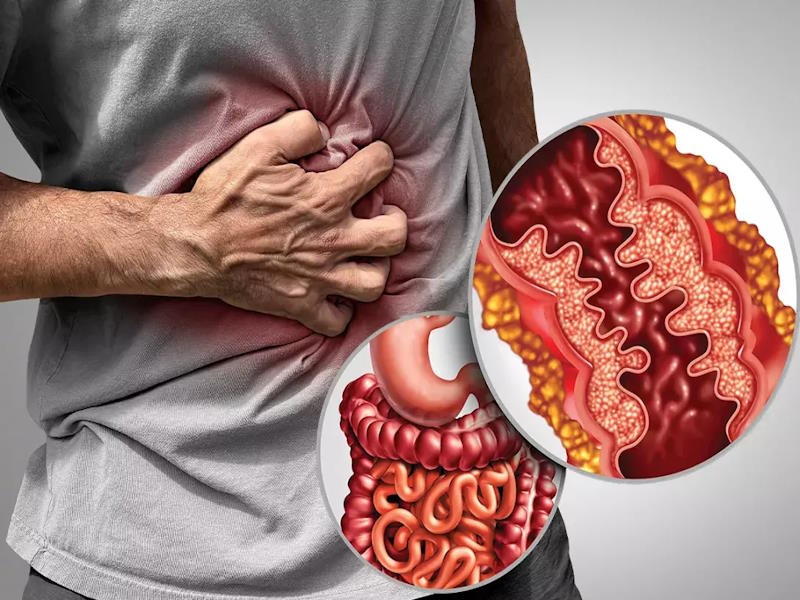

Crohn's disease

Crohn's disease Community awareness